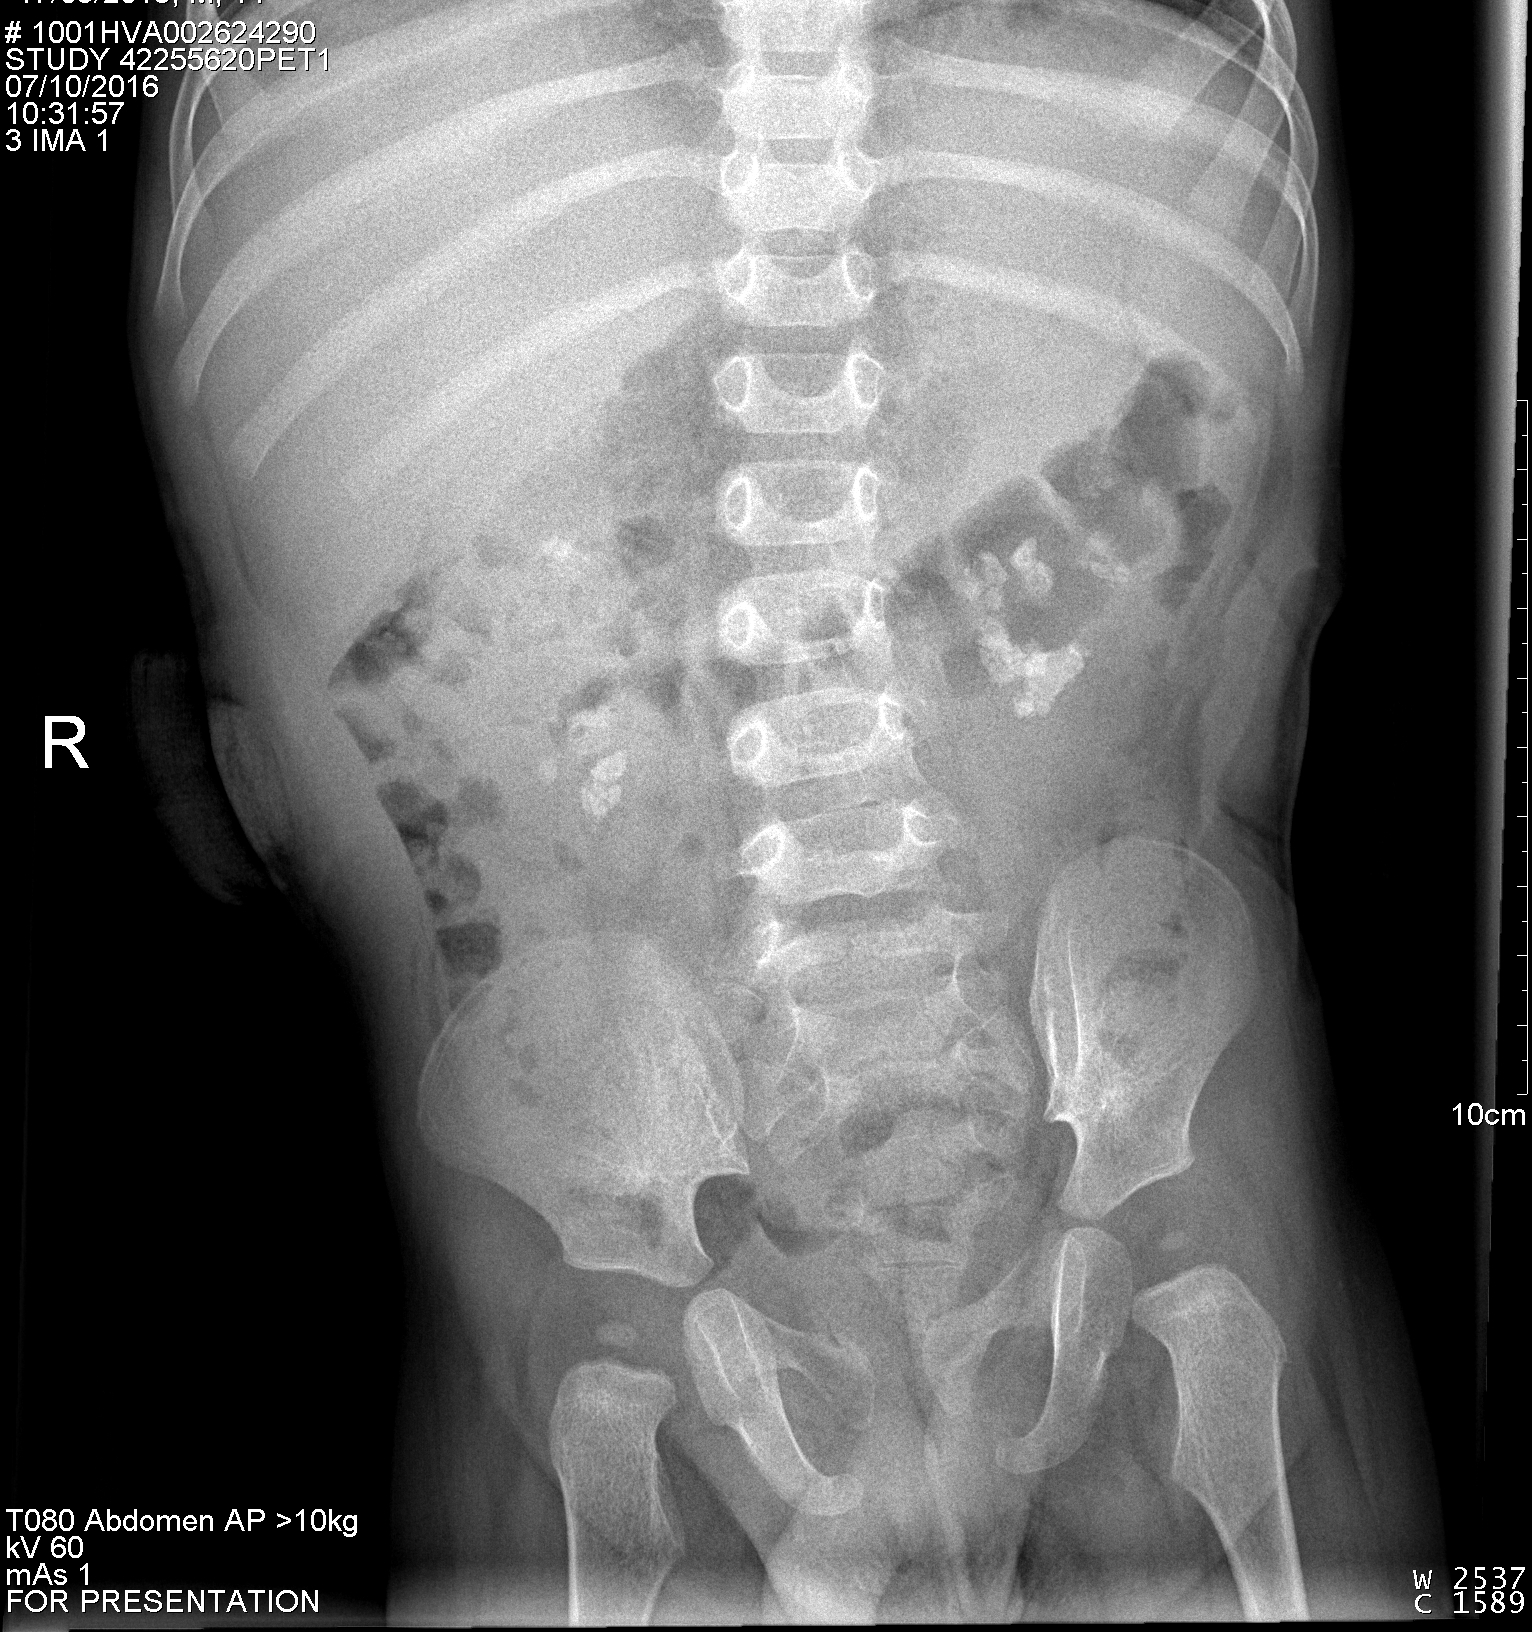

La ecografía es una técnica que permite una exploración bastante completa del aparato urinario, alcanzando una alta sensibilidad para la detección de enfermedades relevantes, sobre todo a nivel renal, vesical y prostático. Para el estudio de los uréteres tiene un inconveniente, y es que solo permite ver las partes más craneales y las más caudales de estos, sin poder estudiar la parte intermedia del uréter. Por ello es necesario emplear otra técnica de imagen para ver si existe afectación de la zona intermedia, como es la radiografía simple de abdomen.

Haz click en las imágenes para verlas ampliadas